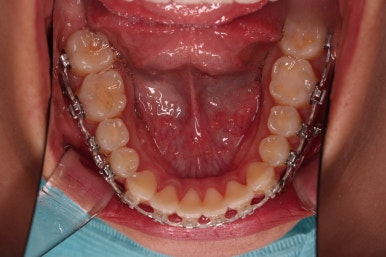

1. 초진 시 입안의 모습 평가

부산연산역치아교정 키다리아저씨치과에 처음 내원했을 당시의 입안의 모습이비다.

앞니 약간, 어금니쪽 약간 삐뚤어진 것, 그리고 위아래 앞니가 약간 뻗쳐 보이는 양상 이외에는 매우 가지런해 보여서 교정치료를 굳이 왜 하시려고 하지? 라고 생각될 정도의 치열 상태였습니다.